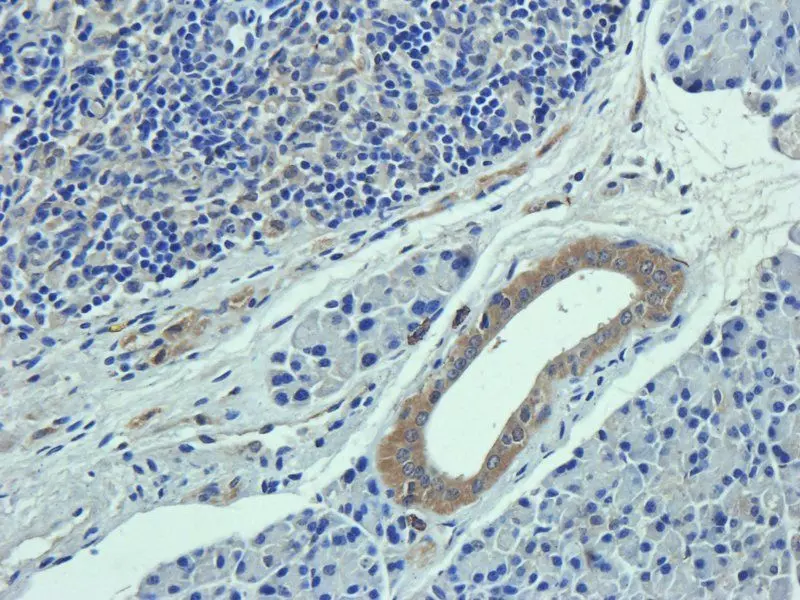

Immunohistochemical staining of paraffin embedded rat skin tissue using Collagen III antibody (2.5 ug/ml) - orb322981.